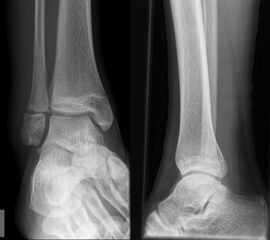

Fugengelenkfrakturen treten typischerweise vor dem 10. Lebensjahr auf, in einer Phase, in welcher die Wachstumsfugen noch weit offen sind. Dieser Frakturtyp betrifft fast ausschließlich den medialen Malleolus. Laterale Frakturen sind extrem selten, teilweise kommt es zu lateralen Bandverletzungen oder Fugenschaftfrakturen der distalen Fibula. Die Frakturlinie verläuft in einer Verlängerungslinie von der medialen Taluskante nach proximal. Häufig stellen sich Verletzungen des Innenknöchels im Röntgenbild schlechter dar, insbesondere wenn die Aufnahmen verdreht sind oder die Ebene der Fraktur bei geringer Dislokation verkippt zur Röntgenebene liegt. Besteht klinisch der geringste Hinweis auf eine Verletzung des Innenknöchels, muss aufgrund der Tragweite der Verletzung durch entsprechende Aufnahmen gegebenenfalls auch Schnittbildverfahren die Verletzung sicher diagnostiziert oder ausgeschlossen werden (Abb. 15).

„Kadiläsion“- Mediale Malleolarfraktur

Bei kindlichen Verletzungen des medialen Malleolus handelt es sich nach L. v. Laer um eine sogenannte Kadiläsion, d.h. eine Verletzung mit hohem Risiko eines schlechten Behandlungsergebnisses bei nicht korrekter Behandlung. Selbst bei optimaler Therapie ist das Risiko für spätere Wachstumsstörungen hoch, sodass diese Verletzungen nicht selten ein juristisches Nachspiel haben. Durch die Verletzung der wachstumsaktiven Zone kann es zu einem vorzeitigen Verschluss der Wachstumsfuge kommen, mit entsprechendem Fehlwachstum. Das Risiko eines vorzeitigen Verschlusses der Wachstumsfuge korreliert mit dem Ausmaß der Schädigung der wachstumsaktiven Zone. Ab dem 13. Lebensjahr wird das Risiko bei reduzierter Wachstumsaktivität zunehmend geringer.

Fugengelenkfrakturen können die Wachstumsfuge durchkreuzen (Abbildung 16a), ohne oder nur mit minimaler Beteiligung der Fuge sehr weit medial liegen (Abbildung 16b) oder durch die Fuge auslaufen (Abbildung 16c). Relevant für die Wachstumsprognose ist weniger die Form der Fraktur, sondern das Alter des Patienten zum Zeitpunkt des Traumas sowie das Ausmaß der Schädigung der Wachstumsfuge, wobei eine Korrelation mit dem Ausmaß der Dislokation besteht.